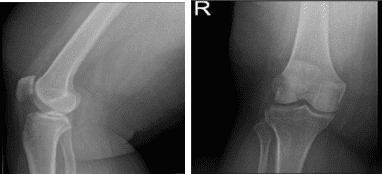

Right Knee X-ray AP Lateral and Oblique

MRI-3T Right Knee Non-contrast

MRI results were presented and shown that there is a radial tear through the posterior horn of the medial meniscus. Tricompartmental cartilage loss, worst in the medial compartment where there is a focal full-thickness chondral defect. There is moderate partial-thickness patellar cartilage loss. Small joint effusion and Baker’s cyst.